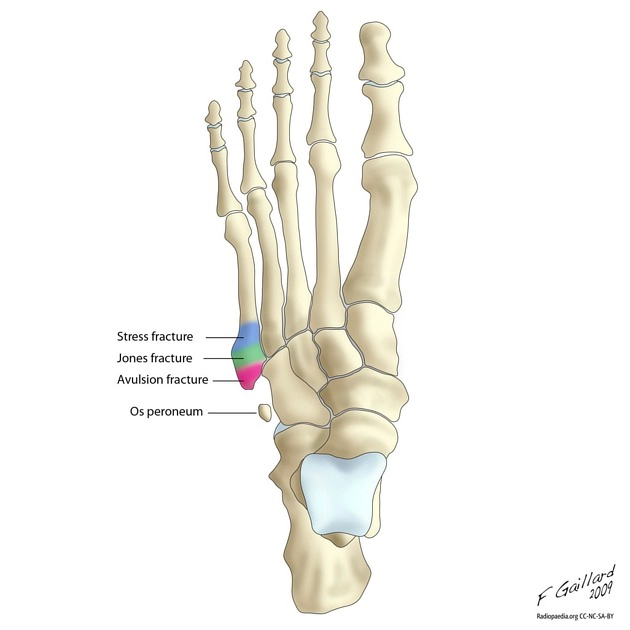

Gãy Jones (Gãy đầu gần xương bàn chân số 5)

16/03/2026

Gãy bong lồi củ xương bàn chân số 5 (pseudo-Jones fracture)

Gãy do mỏi ở xương bàn chân số 5 (Stress fracture of the 5th metatarsal)